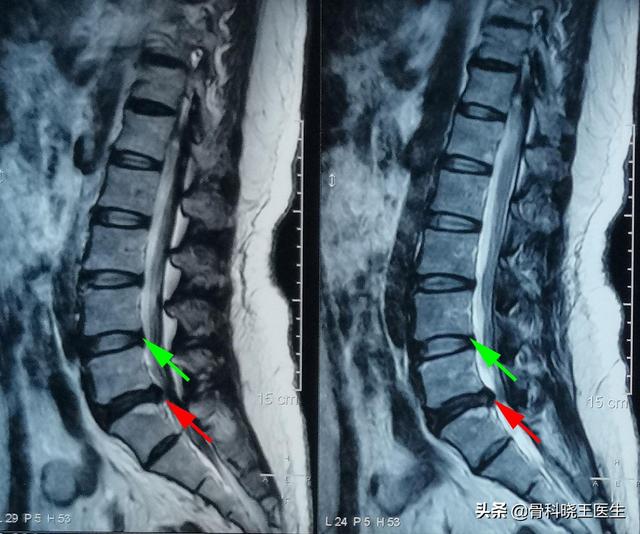

椎間板ヘルニアとは、様々な原因で椎間板の環状線維が破れ、髄核が突出した状態のことです。 軽度の椎間板ヘルニアであれば、抗炎症作用により収縮することが可能です。しかし、中等度から重度のヘルニアでは、椎間板のヘルニア部分が収縮することは非常に困難です。

椎間板ヘルニアの急性期は、安静と療養、硬いベッドでの睡眠、消炎鎮痛が中心となり、浮腫期が終われば圧迫症状はかなり軽減します。しかし、縮小して以前のレベルに戻るのは本当に難しい。この時、治療の主な臨床的治療、つまり、症状が治まることで、椎間板ヘルニアを縮小させることを過度に追求しないでください。

リカバリーが難しい!これは椎間板の構造によって決まります。腰椎椎間板は全体ではなく、内側の髄核と外側の線維性環状骨からなり、その後ろに靭帯があります。したがって、椎間板ヘルニアは椎間板全体のヘルニアではなく、椎間板から髄核が徐々に「はみ出した」状態です。初期の段階では、髄核の周りの線維輪は破壊されていないので、腰椎椎間板「膨隆」と呼ぶことができ、後期になると、髄核が周りの線維輪を突き破り、脊柱管にまで入り込んで神経を圧迫すると、腰椎椎間板「ヘルニア」となります。したがって、腰椎椎間板ヘルニアが起こるということは、腰椎椎間板の周りの線維輪の構造が「ヘルニア」と同じように破壊されたということであり、ヘルニアになった髄核は非常に戻りにくいのです。また、髄核を包んでいる線維輪は血行が悪いだけでなく、治りも悪いので、髄核がかろうじて回復しても、また簡単にヘルニアになってしまいます。